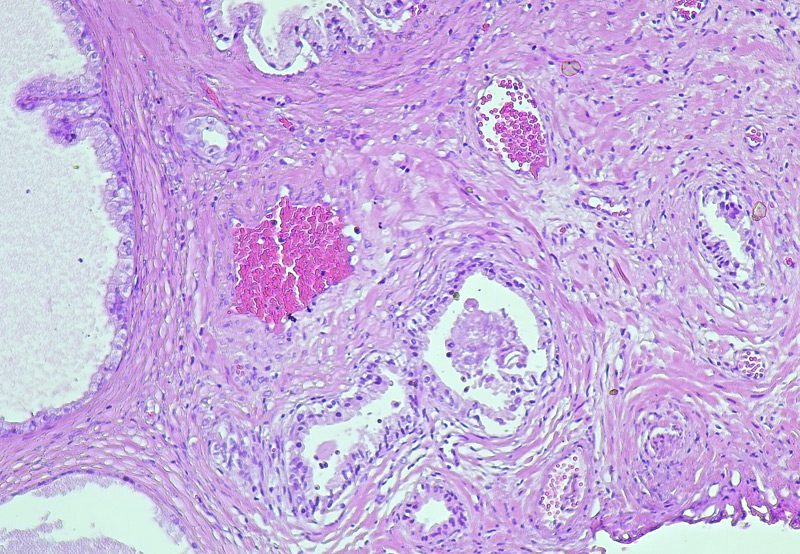

Benign Prostatic Hyperplasia (BPH), also called benign prostatic hypertrophy, is a non-cancerous enlargement of the prostate gland that commonly affects men as they age. The prostate surrounds the urethra—the tube that carries urine from the bladder out of the body. As the prostate enlarges, it can press against the urethra and interfere with normal urinary flow, leading to symptoms that affect both quality of life and urinary function.

Causes of Benign Prostatic Hyperplasia

The exact cause of BPH is not fully understood, but it is closely linked to hormonal changes associated with aging. As men grow older, levels of testosterone decrease while estrogen levels may remain the same or increase. This hormonal imbalance is believed to contribute to prostate growth. In addition, dihydrotestosterone (DHT), a testosterone-derived hormone, may accumulate in the prostate and encourage cell growth.